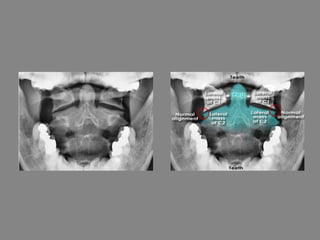

C-spine normal anatomy - Open mouth view

• This view is considered adequate if it shows the

alignment of the lateral processes of C1 and C2

• The distance between the peg and the lateral masses

of C1 should be equal on each side

• Note: In this image the odontoid peg is fully visible

which is not often achievable in the context of

trauma due to difficulty in patient positioning

• The distance between the peg and the lateral processes is not

equal - compare A (right) with B (left)

• This is because when the image was acquired the patient's

head was rotated to one side

• Alignment of the lateral processes can still be assessed and is

seen to be normal